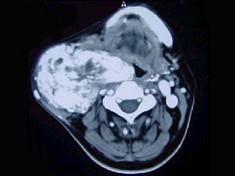

45岁,男性,颈部渐进性增大包块,CT增强扫描如图所示,请选择最可能诊断 ( )A、颈动脉体瘤B、甲状腺癌C、颈动脉夹层瘤D、神经鞘瘤...

问题 45岁,男性,颈部渐进性增大包块,CT增强扫描如图所示,请选择最可能诊断 ( )

选项 A、颈动脉体瘤 B、甲状腺癌 C、颈动脉夹层瘤 D、神经鞘瘤 E、颈部肿大淋巴结

答案 A